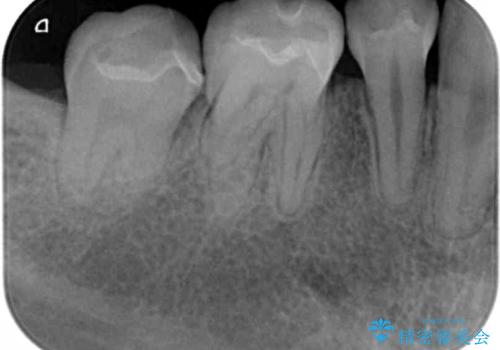

- 矯正治療終了後、前々から気になっていた笑った時に見える銀歯を白くしたいと希望され来院されました。

銀歯を拡大鏡下で丁寧に除去したのち、小さな虫歯も除去し精密で適合の良いセラミックインレーによる再修復を行います。